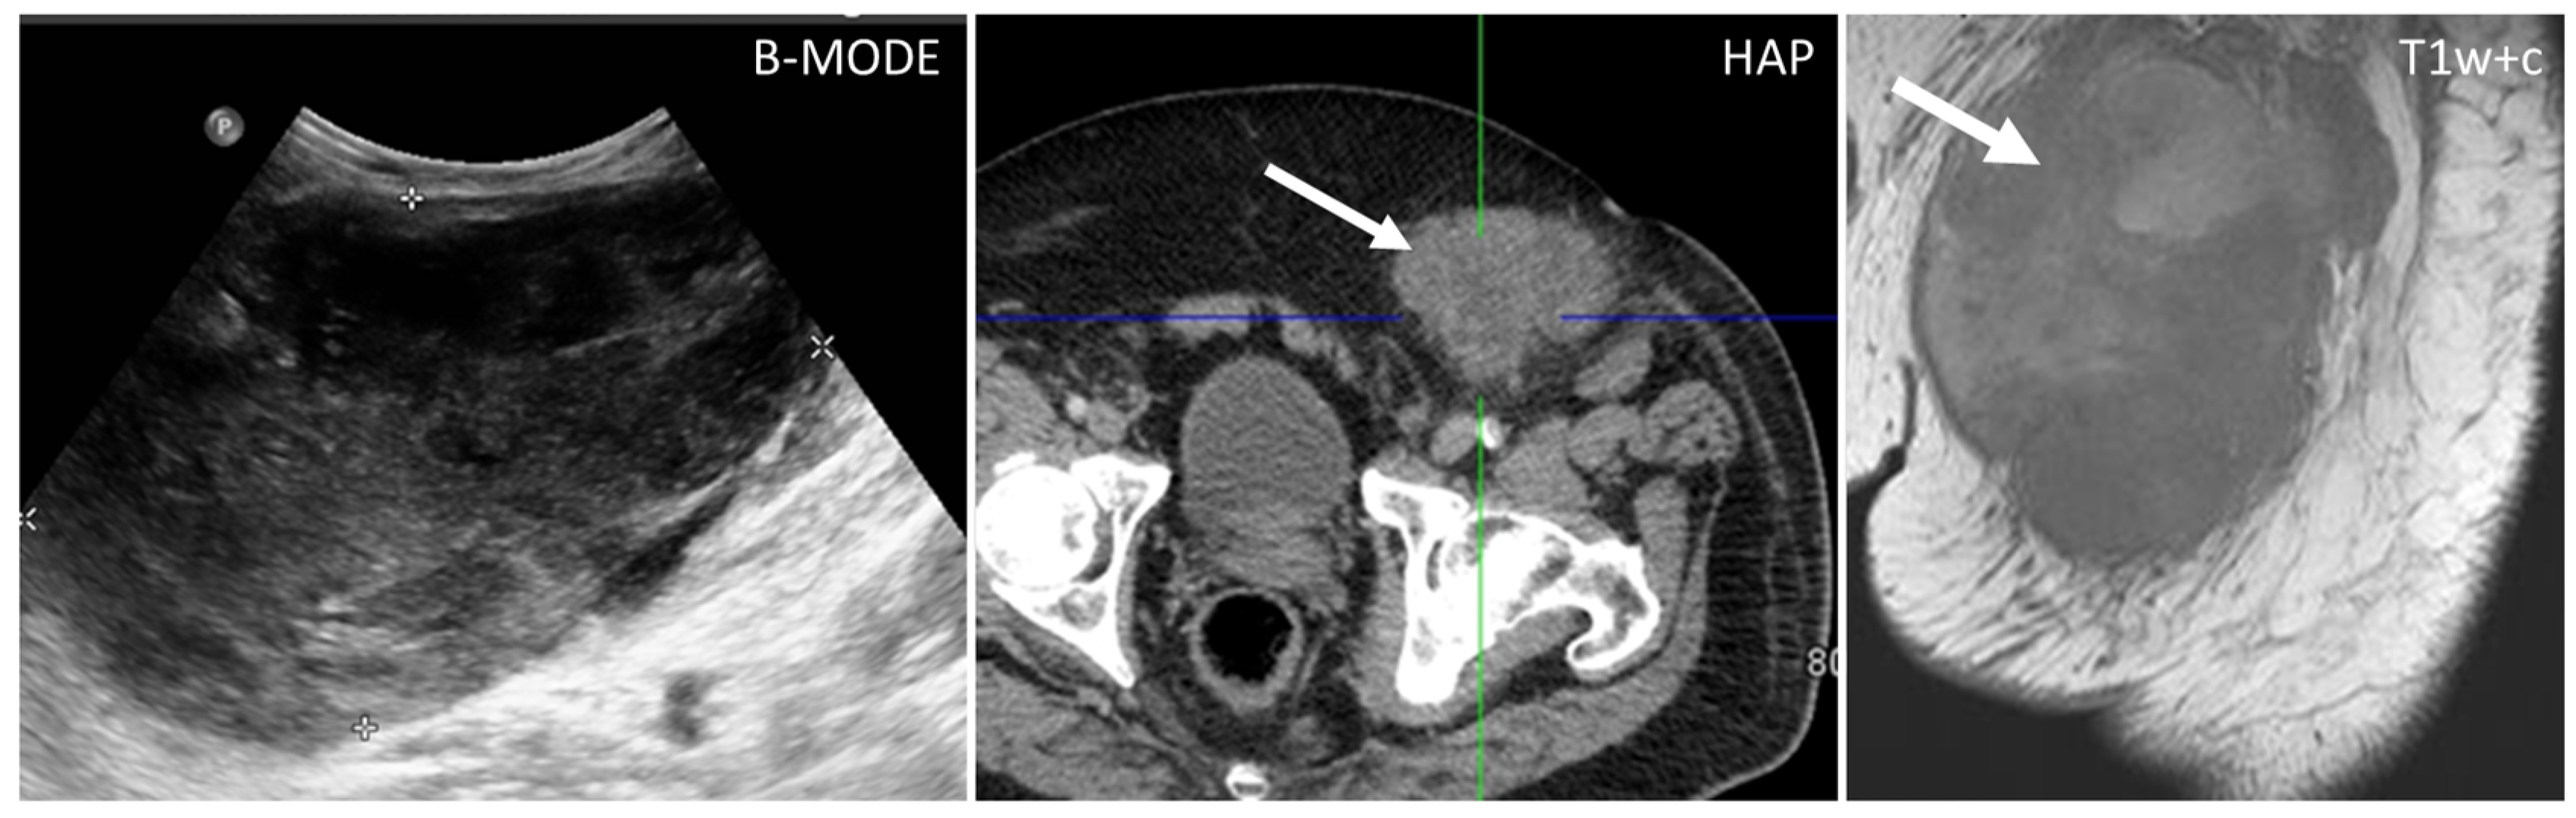

- Gastrointestinal Stromal Tumors (GIST): either primary (extraintestinal GIST, “EGIST”) [25,26] or secondary GIST of the abdominal wall are rare. When extended (>5 cm), GIST may have an aggressive behavior [25]. CT is the imaging modality of choice, showing heterogeneous vivid enhancement, and variable amount of necrosis. Peculiar findings include calcifications and cystic degeneration [27,28,29].